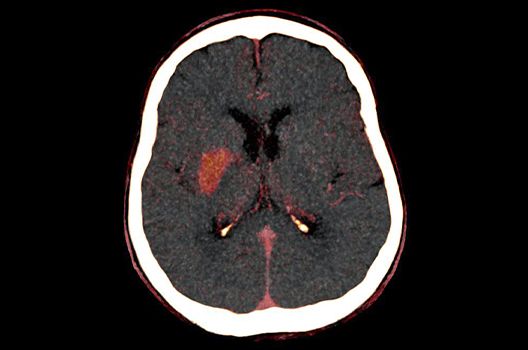

Die Schwerpunkte in der CT-Forschung liegen in der Bildnachverarbeitung, der Dosis- und Artefaktreduktion sowie der quantitativen und automatisierten CT-Bildanalyse.

Die Computertomographie (CT) ist ein Verfahren, bei der mit Hilfe von Röntgenstrahlung Schnittbilder des Körperinneren angefertigt werden. Unser Bestreben ist es hierbei, bei möglichst niedriger Strahlendosis eine bestmögliche Bildqualität zu erzielen. Eine zunehmend große Rolle in der radiologischen Forschung spielen zudem die Automatisierung in der Bildanalyse und die computergestützte Auswertung großer Datenmengen, wie sie bei einer CT-Untersuchung anfallen. Wir arbeiten in enger Kooperation mit den Geräteherstellern zusammen und sind daher maßgeblich an der Entwicklung und Erprobung neuer Techniken beteiligt.